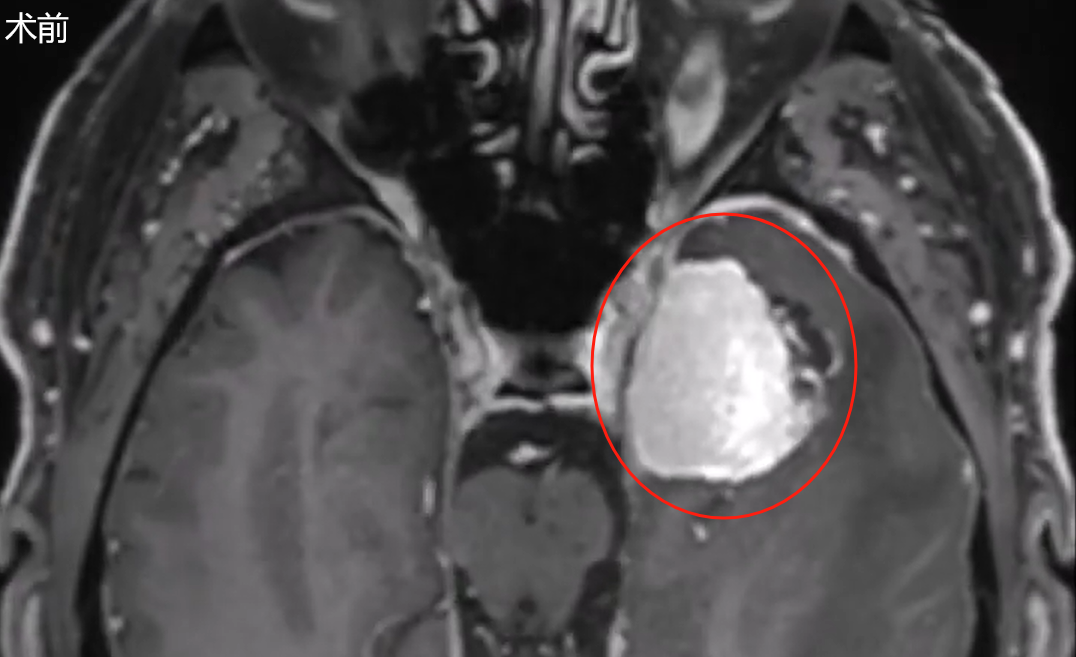

“传统观念认为开颅手术需要在头颅上打开较大骨窗,但实际手术切口却非常微小,术后第6天即完成拆线并顺利出院。”一位64岁男性患者因出现记忆力减退及癫痫发作症状,经检查发现左侧海绵窦外侧壁存在病变,影像学同时显示病变周围水肿及颞叶受压。

肿瘤定位于海绵窦外侧壁,使得经典翼点入路成为福洛里希教授初期考虑的手术方案。但该入路存在固有局限性,包括需要对正常软组织进行广泛剥离、可能引发颞肌疼痛、影响美观、术中需牵拉脑组织以及导致颞叶回缩等问题。

出于对颞叶保护的高度重视,并结合肿瘤未包绕血管、患者秃顶但眉毛浓密的具体情况,福洛里希教授最终决定采用经眶入路,亦即通过眉毛区域实施肿瘤切除。此入路能够提供更优的手术视野与充足的操作空间,有效降低危险牵拉。同时,它为显微镜与内镜的联合应用创造了极佳的可视化条件与操作便利性。

术后影像学复查证实肿瘤获得全切,且未出现任何手术相关并发症。患者未发生新的神经功能缺损,并于术后第6天拆线出院。